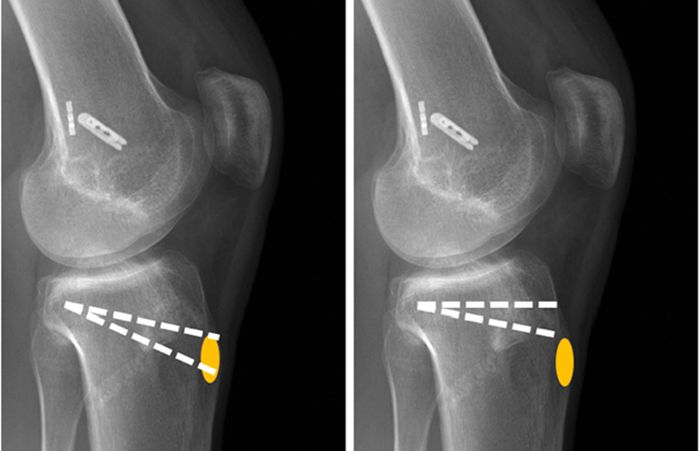

Osteotomy surgery

DOME Shaped

In this method, the osteotomy is performed in the form of a sphere and a bowl around the joint, the lower part of the osteotomy site is rotated around the vertical axis - after the osteotomy and breaking the spherical and semicircular bone, and after correcting the deviation of the organ axis and deformity, it is fixed. In this method, there is no shortening and lengthening of the limbs and it is technically more difficult.

Osteotomy surgery

Close wedge

In this operation, a triangle or wedge of bone is removed from under the healthy part of the knee in the leg or the lower part of the thigh, and after closing the gap, the extension of the limb is corrected and fixed with a device. (The amount of bone removed depends on the size of the deformity and needs to be modified differently). In this method, the body becomes slightly shorter.

Osteotomy surgery

Open wedge

Open wedge osteotomy surgery is a surgical procedure used to treat certain bone problems. In this method, the surgeon opens the required area on the bone to access the bone. Then he removes a part of the bone and makes the desired changes.